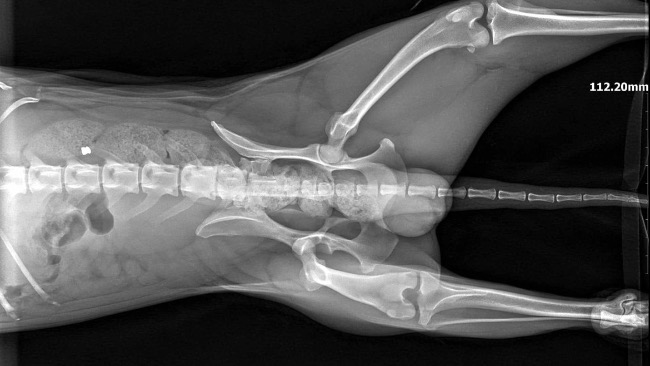

Dnia 24.11 wykonano badanie RTG z powodu kulawizny prawej tylnej kończyny.

Na zdjęciach stwierdzono wystawienie główki kości udowej prawej z panewki stawu biodrowego. Zalecono zabieg resekcji (usunięcia) główki kości udowej w celu wytworzenia stawu rzekomego.